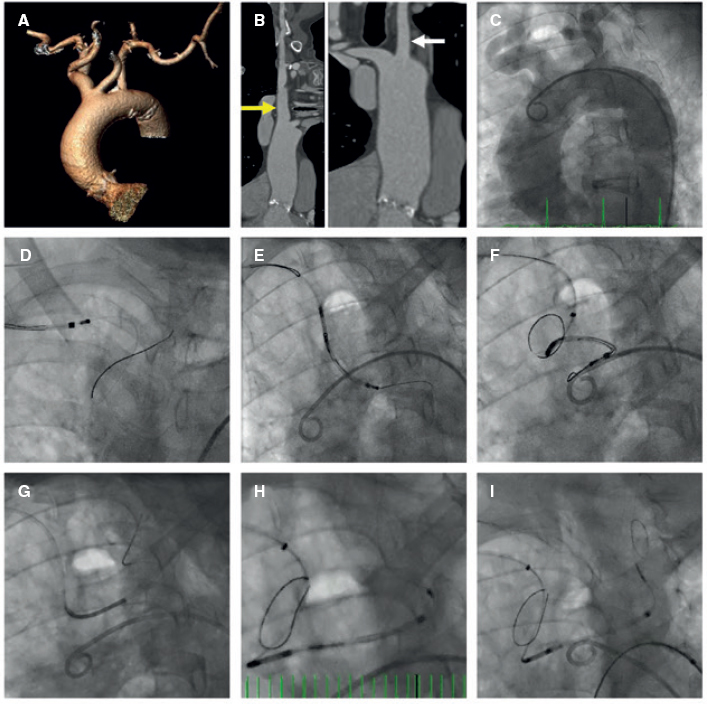

An 84-year-old female with severe aortic stenosis and previous non-disabling stroke was referred to undergo transcatheter aortic valve replacement (TAVR). The 3D computed tomography performed revealed the presence of a type 9 aortic arch with severe tortuosity (figure 1A). It was decided to protect the supra-aortic branches with suitable diameters to be able to use the Sentinel Cerebral Protection System (Boston Scientific, Marlborough, MA, United States). Manipulation length in the left common carotid artery (LCCA) was of, at least, 8 cm which is the distance between the proximal filter and the Sentinel distal edge. Figure 1B: yellow arrow: brachiocephalic trunk, 12 mm-diameter. White arrow: LCCA, 7 mm-diameter. This cerebral protection device (CPD) has a proximal filter for brachiocephalic trunk diameters between 9.0 mm and 15 mm and a distal filter for LCCA diameters between 6.5 mm and 10 mm. The angiography of the aortic arch is shown on figure 1C. This dual-system-filter basket was tried unsuccessfuly over a 0.014 in guidewire despite the use of an articulating sheath (figure 1D-F). After several attempts, a multipurpose catheter was used to engage the LCCA (figure 1G). Using a 300 cm 0.014 in guidewire, the multipurpose catheter was exchanged for the CPD which allowed its suitable deployment (figures 1H,I). The TAVR was performed successfully and the CPD was retrieved (video 1 of the supplementary data). Informed consent was obtained from the patient.

Figure 1.

The major concern is how to balance the risk of stroke after TAVR and the risk of manipulation with guidewires/catheters in supra-aortic arteries. Thus, the rigorous study of the computed tomography scan is the key factor for strategic planning purposes. This was an alternative approach to achieve the placement of a Sentinel device using a multipurpose catheter in a complex aortic arch.